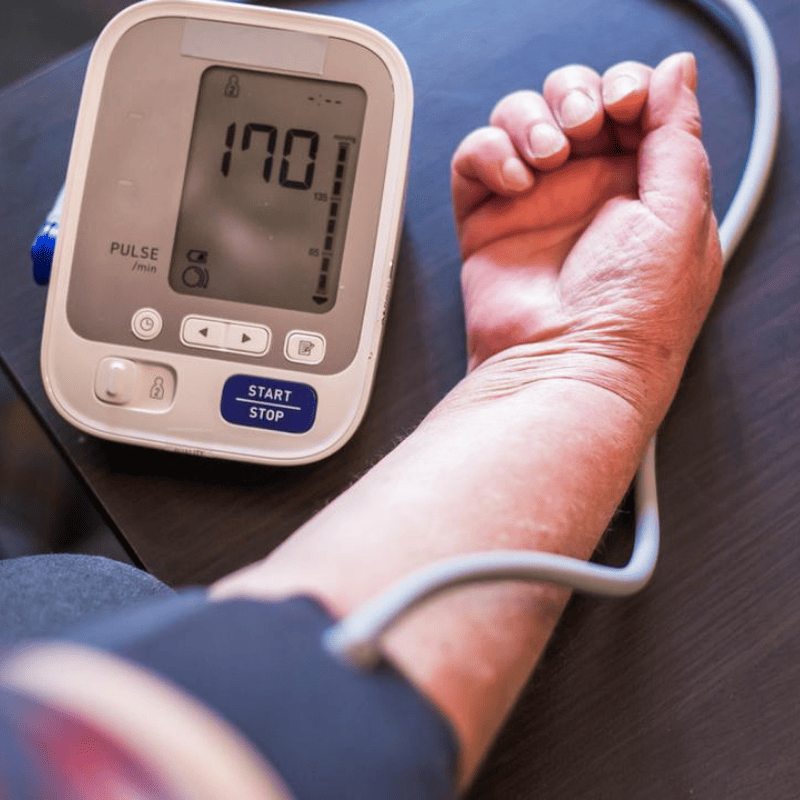

Neuropati Hipertensi

Darah tinggi yang tak terkawal boleh rosakkan saraf halus, buat isyarat dari otak ke zakar jadi lemah dan menjejaskan ereksi serta ejakulasi.

LEBIH PARAH jika belarutan sehinggga menyebabkan masalah Peripheral Artery Disease (PAD).